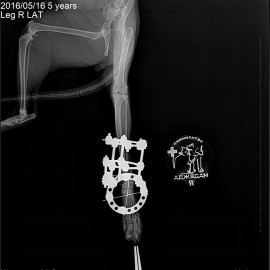

Наш пациент, кот, по кличке Архип.

Обратились к нам после автотравмы с жалобами на отсутствие опороспособности на правую заднюю лапу.

Было проведено рентгенологическое исследование.

Поставлен диагноз: перелом правой голени, вывих правого голеностопного сустава. Была проведена операция: остеосинтез правой голени, остеосинтез правого голеностопного сустава.

Снимок 3-4 после операции.